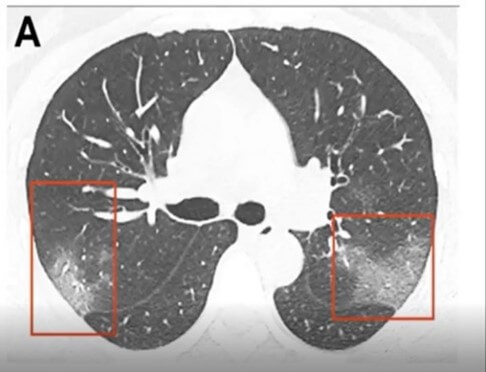

CT is still the gold standard for lung imaging, but it’s difficult to access a CT when you have a critical care patient. The volume of COVID patients, on top of limited access to CT machines, makes this method less than ideal for evaluating the lungs. Interestingly, in about 50 percent of patients, there are no findings between 0-2 days after the onset of symptoms of COVID. It takes about 3-5 days before CT findings are positive. When they are positive, they have bilateral peripheral and basal ground glass opacities (Figure B) in about 50-75 percent of patients. The distribution through the lungs is typically in the lower part of the lungs, but as the disease severity evolves, the CT findings can also be much more extensive.

Figure B. CT scan of a positive COVID-19 patient. The red squares highlight the bilateral peripheral and basal ground glass opacities.